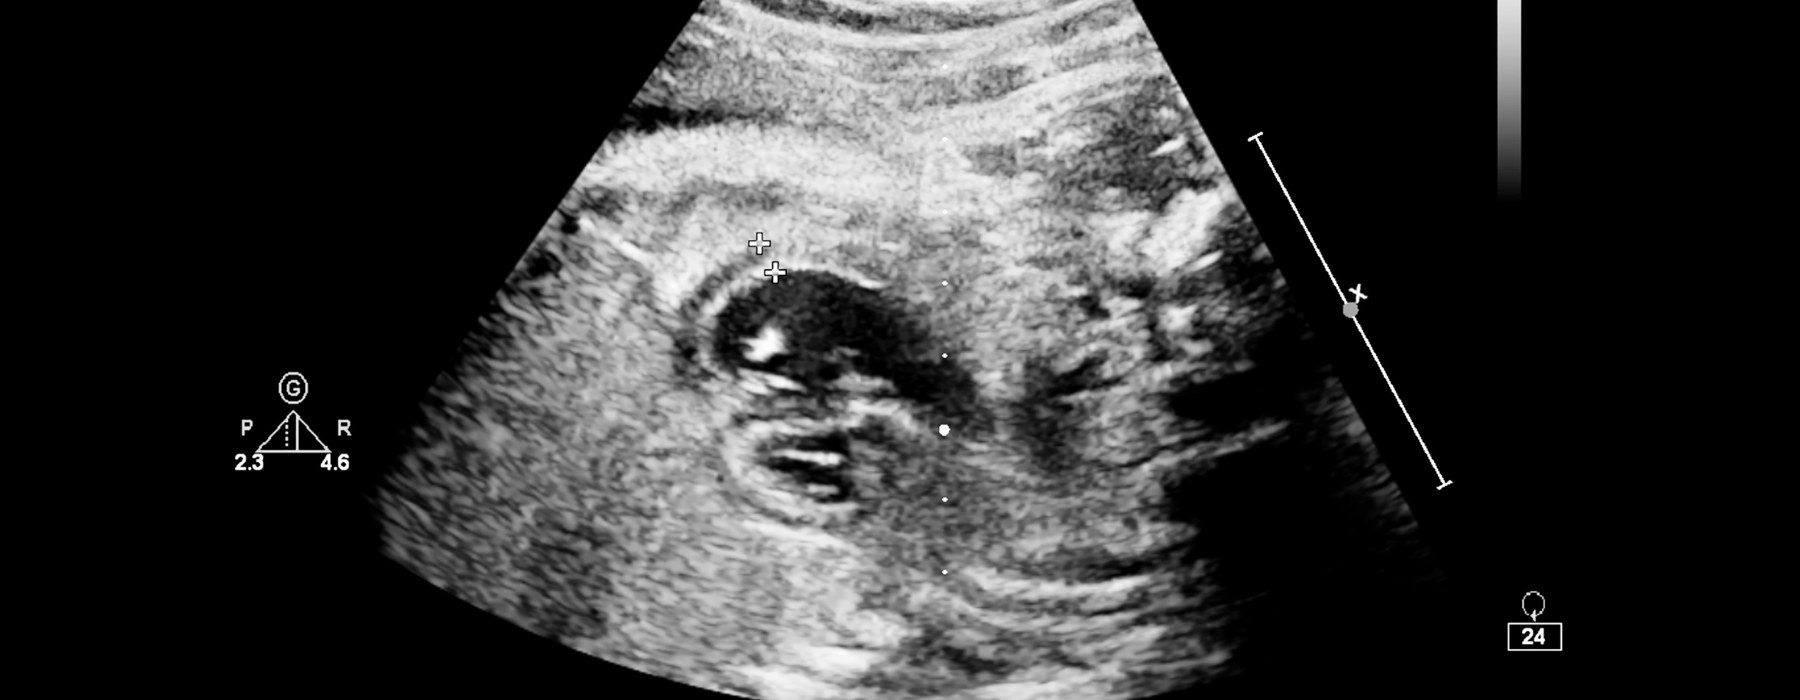

O ecocardiograma utiliza ultrassom para gerar imagens do coração em tempo real, ajudando médicos a analisar estruturas cardíacas, válvulas e o fluxo sanguíneo com precisão.